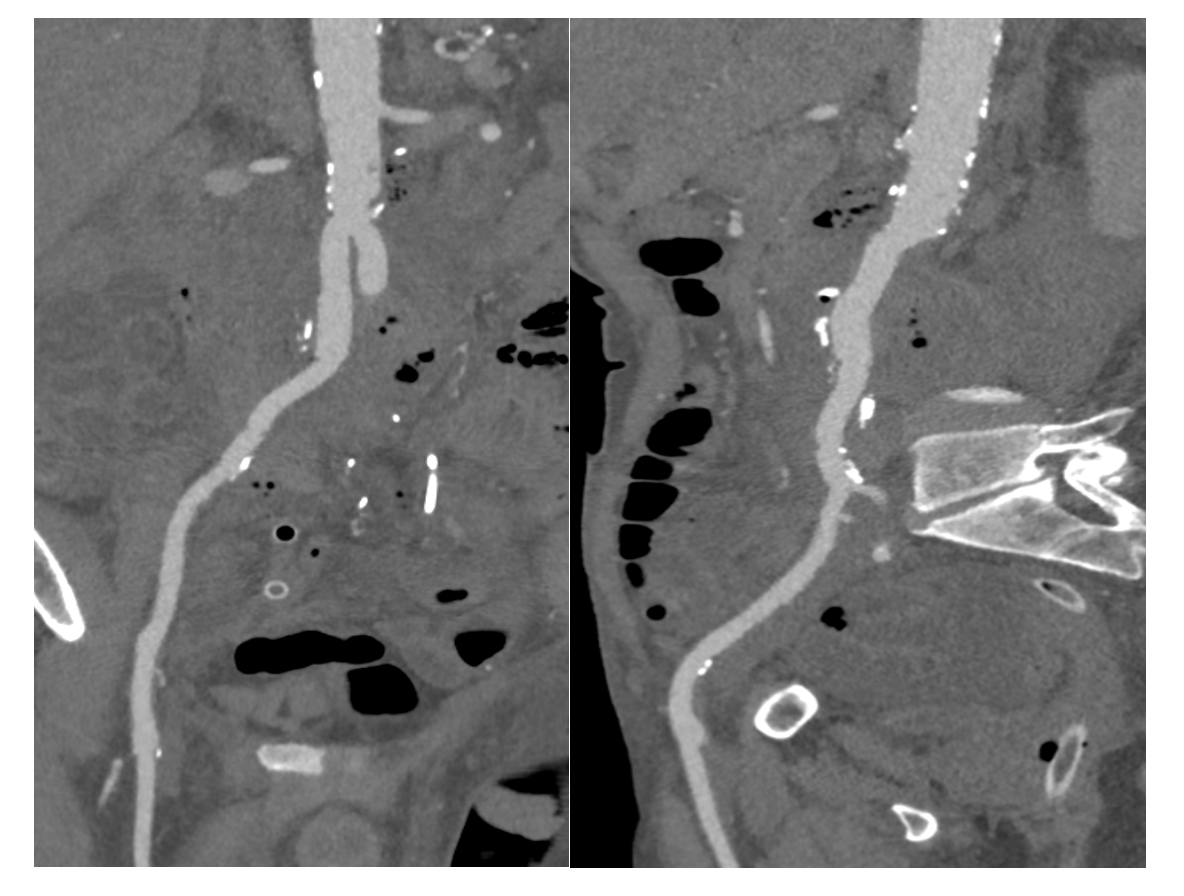

Total colposcopy with resection of 3 polyps at the left colon showed tubular adenoma with low-grade dysplasia. Bronchoscopy with bronchoalveolar lavage as well as serology of human immunodeficiency virus, hepatitis B and C, Lyme disease, Epstein-Barr virus, prostate-specific antigen, and lactate dehydrogenase were negative. The patient was diagnosed with C. fetus colitis and was given IV amoxicillin clavulanate (1 g 3 times/day for 10 days). One month later, he was readmitted for recurrence of the same symptoms. This time, testing showed a patent biologic inflammatory syndrome (anemia, 9.4 g/dL; thrombocytosis, 1038 G/L; and CRP, 229 mg/L). An abdomino-pelvic CT scan identified left pyelocaliceal dilation without a detected obstacle and an empyema measured at 35 mm plus abscessed collections measuring at most 25 mm. The aortic aneurysm had increased in diameter, reaching 65 mm x 40 mm and 79 mm at its greatest axis (Figure 1). Ureterohydronephrosis of the left kidney was also identified. Findings on transthoracic echocardiogram were normal. A transesophageal echocardiogram ruled out endocarditis. Blood culture grew C. fetus, and urine and feces cultures were sterile. Ultimately, strong IV antibiotic therapy was immediately initiated based on a consult from infectious disease specialists (amoxicillin clavulanate 2 g/4 hours and gentamicin 180 mg/24 hours). Given the high risk of rupture, an urgent surgical repair of the AAA was considered, preceded by the placement of a double J stent to treat ureterohydronephrosis. Through a midline laparotomy, an excision of the mycotic aneurysm and establishment of vascular continuity using allograft bypass in the infrarenal aortic bilateral common iliac arteries were performed (Figure 2). Pre- and post-operative courses were uneventful except for a blood transfusion.

After 48 hours of surveillance in the intensive care unit, the patient was transferred to the internal medicine and infectious disease departments for management of undernutrition and close monitoring of antibiotic response. As cultures of all surgical specimens yielded C. fetus, the antibiotic regimen was continued for 6 weeks after surgery. Gentamycin was suspended after 2 weeks of treatment. The patient was discharged home on his 16th postoperative day. Findings of clinical and biological systemic inflammatory syndrome were completely regressed at the first follow-up (first month). The angio-CT scan showed no anomalies (Figure 3). The patient later benefited from removal of the double J stent.